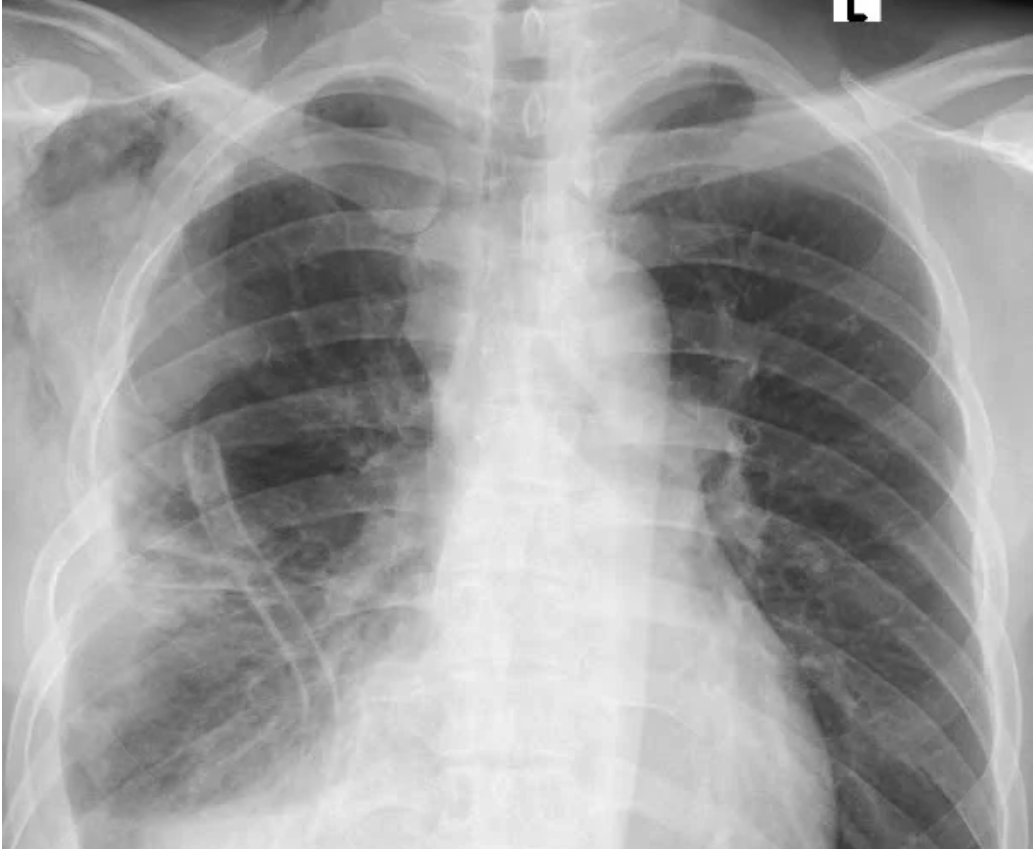

Hình trước phẫu thuật (bên trái): Khối u xâm chiếm khoang ngực, gây xẹp gần như toàn bộ phổi phải

Qua thăm khám và chụp cắt lớp vi tính lồng ngực, các bác sĩ phát hiện khối u trung thất khổng lồ nằm lệch trong khoang màng phổi phải, chèn ép gây xẹp gần như toàn bộ phổi phải, đẩy lệch cơ hoành.